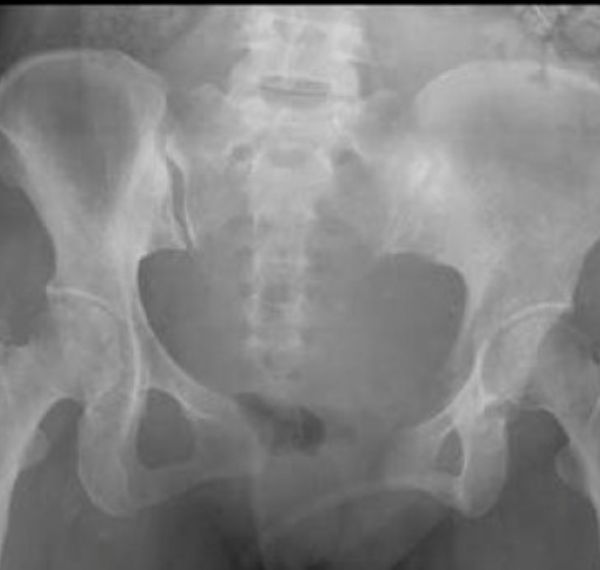

Total Hip Replacement

Prosthetic replacement of a painful or damaged hip joint.

Who it’s for: Those with hip arthritis, injury, or degeneration.

Key Benefits: Relieves stiffness, improves walking comfort, and supports long-term joint health.